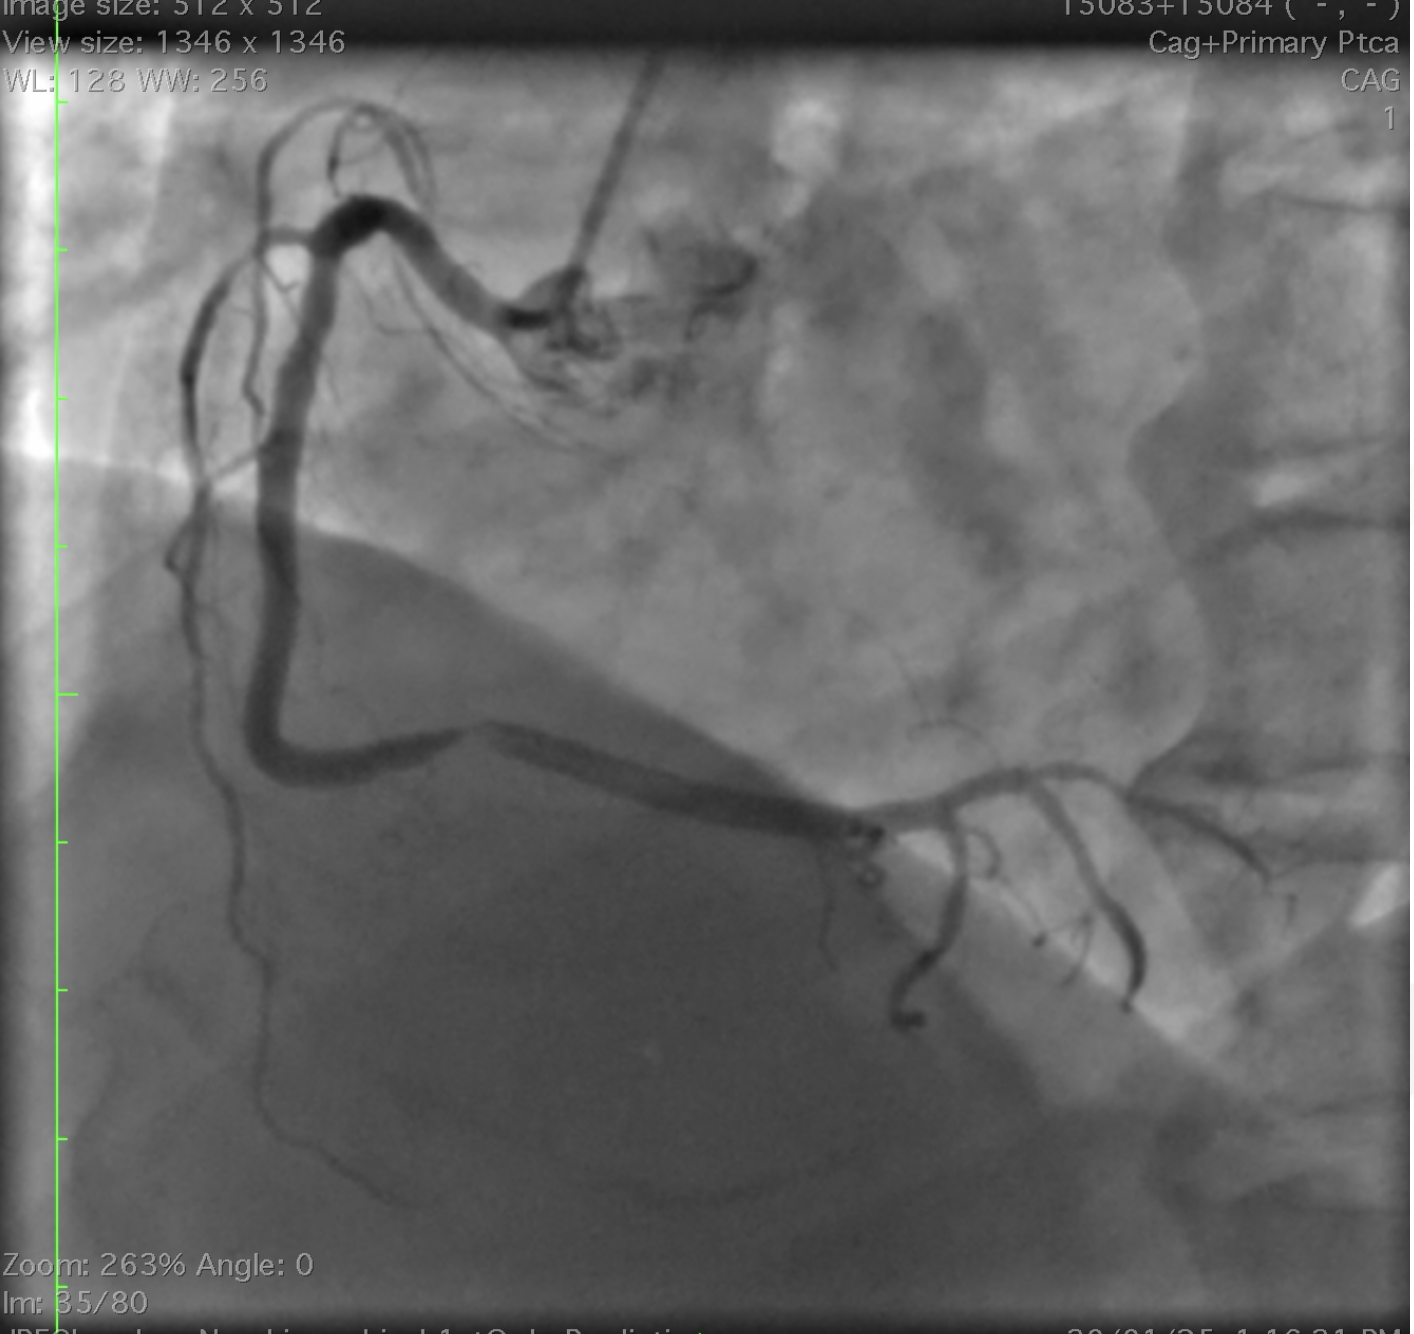

A 67 year old male presented to emergency room with chest pain of 1 hour duration. Chest pain was central radiating to left arm and is associated with nausea, vomiting and diaphoresis.Electrocardiogram showed ST elevation in lead 2, 3, aVF sugesting inferior wall myocardial infarction (Figure 1). Echocardiogram showed no mechanical complications and an ejection fraction of 50 % with inferior wall hypokinesia. He was treated with dual antiplatelets, statin and low moilecular weight heparin

He was immediately shifted to catheterization laboratory and angiogram showed mild plaque in left anterior descending artery (Figure 2)(Video 1) and significant stenosis In distal right coronary artery with additional mild plaque proximally (Figure 3) (video 2).